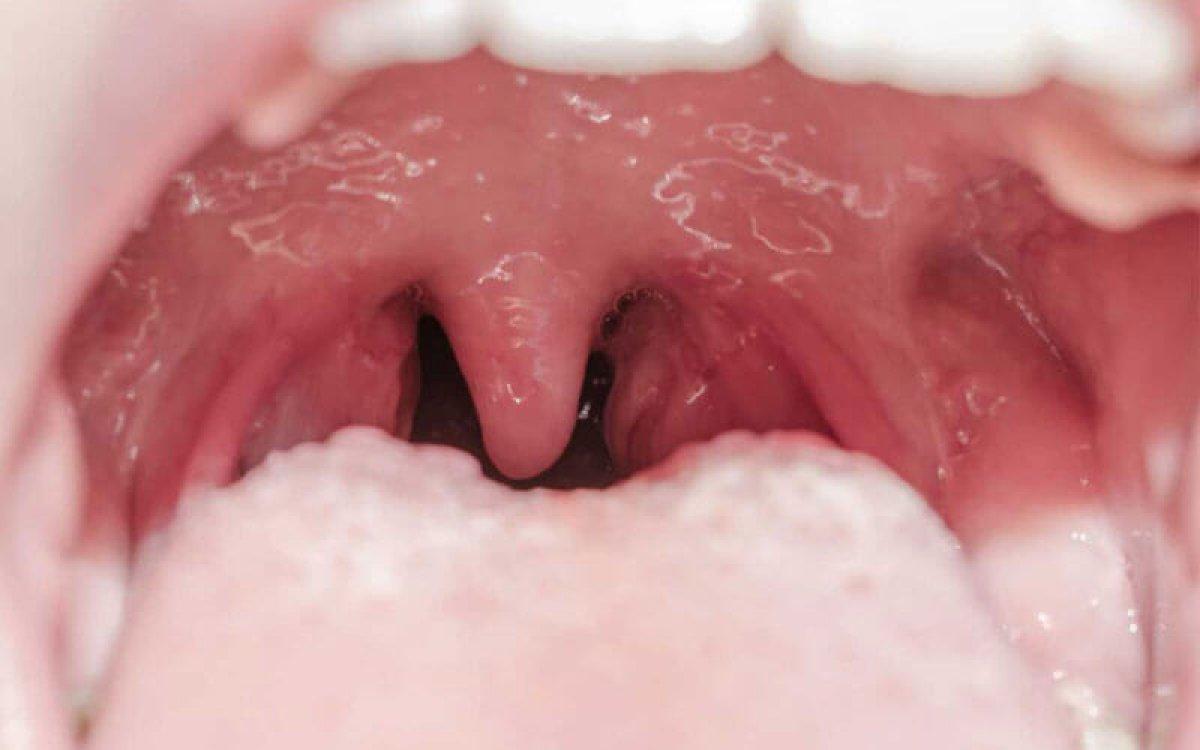

Damağın arka kısmında sallanır halde bulunan, ağzın tam olarak açılmasıyla birlikte görülen, palatine uvula olarak da adlandırılan bir et parçası olan "küçük dil", aslında et parçasından çok daha fazlası.

Konuşma ve yutkunma sırasında yukarı doğru hareket ederek havayolunu kapatan bir kapakçık görevi üstlenmektedir. Böylece buruna ve genize herhangi bir cismin kaçmasını engellemektedir.

Sesi titreştirme özelliği bulunmaktadır. Bu nedenle telaffuz etmeyi sağlar.

Küçük dil sesin düzgün çıkmasını sağlar. Aynı zamanda harflerin belirgin bir şekilde söylenmesini de sağlar.

Küçük dil de tıpkı bademcik ve damak gibi vücuda giriş yapan ağız yolu enfeksiyonları ve bakteriler ile savaşır.

Öğürme refleksini sağlar.